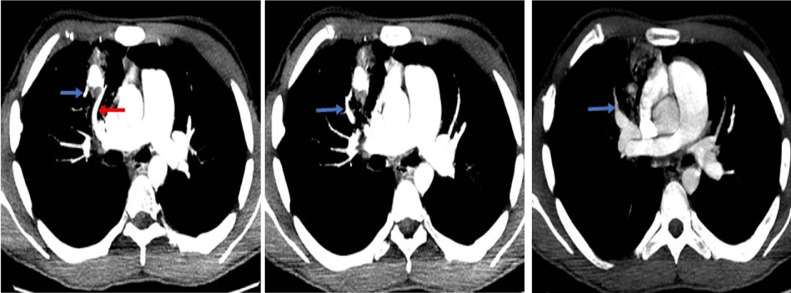

Fig. 2.

CT pulmonary angiography: Axial images sequence. The artery of the anterior segment of the right upper lobe (red arrow) is the vascular structure from which the pseudoaneurysm originates. Additionally, it presents a drainage vein (blue arrows), a branch of the right superior pulmonary vein, which confirms an abnormal communication between an arterial and a venous structure, configuring a fistula.